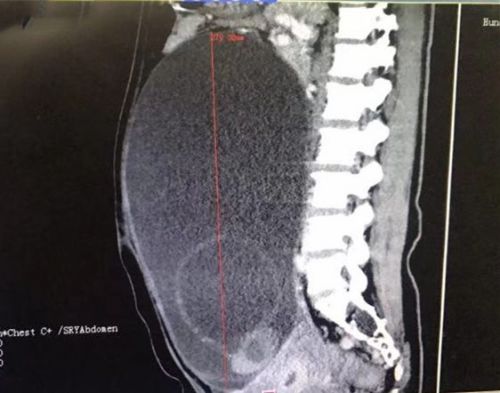

全腹ct显示肿块巨大。

入院完善腹部CT结果显示,比篮球大的肿瘤不仅占据盆腔,还长到腹腔内,考虑左侧卵巢来源黏液性囊腺癌的可能性大。完善术前准备后,3月1日,闵小佳带领手术团队在全麻下为陈女士施行卵巢癌全面分期手术,将被肿瘤侵犯的子宫、双侧附件、大网膜、阑尾切除,并进行盆腔淋巴结清扫和盆腔粘连松解。手术过程顺利,术中发现左侧卵巢囊样增大至约30×25×28cm3大小,切下来的肿瘤装了整整一脸盆,足有10余斤。